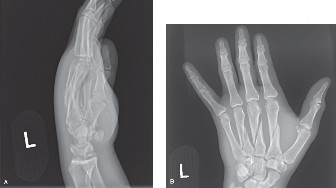

CASE 12 A 24-year-old, law student injured her left index finger during a volle…